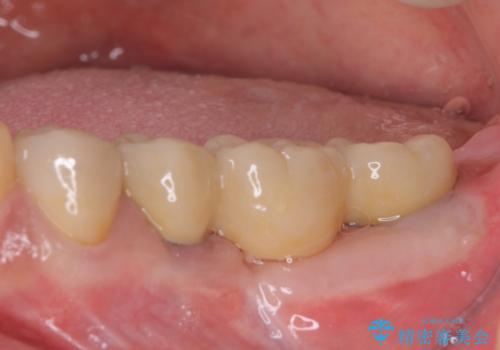

仮歯がない状態を極力避けたいとのことで、外科処置を少しずつ進めていくことになり、治療期間は2年間を要しました。

治療後は痛みなどなく、快適に噛めるようになりました。